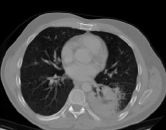

4.1.5 Chest CT

Chest CT scans play a relevant role in diagnosing a wide range of thoracic diseases, from infections to malignancies. By analyzing those scans, it is possible to detect diseases in the chest region, including pneumonia and cancer. The selected chest CT dataset 555https://www.kaggle.com/datasets/mohamedhanyyy/chest-ctscan-images contains 967 images across normal and three cancer types: adenocarcinoma, large-cell carcinoma, and squamous-cell carcinoma. Figure 6 provides a visual representation of the four highlighted classes.

Table 1 provides a detailed summary of the datasets used in this study, highlighting the total number of images in each dataset, the distribution between training and testing sets, and the specific classes represented. Each dataset corresponds to a particular medical imaging domain with distinct classes relevant to diagnosing specific conditions. Also, Fig. 9 presents a representative image from each dataset, allowing for a visual comparison of the diverse tones, patterns, and textures present across the datasets. Such diversity in visual characteristics highlights the need for a robust model that can handle all image characteristics.